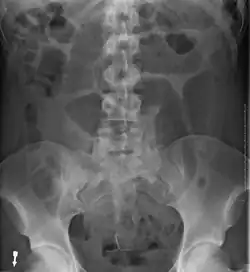

After taking a thorough history, the diagnosis of colonic volvulus is usually easily included in the differential diagnosis. Abdominal plain x-rays are commonly confirmatory for a volvulus, especially if a coffee bean sign is seen. These refer to the shape of the air-filled closed loop of the colon, which forms the volvulus. Should the diagnosis be in doubt, a barium enema may demonstrate a "bird's beak" at the point where the segment of proximal bowel and distal bowel rotate to form the volvulus.